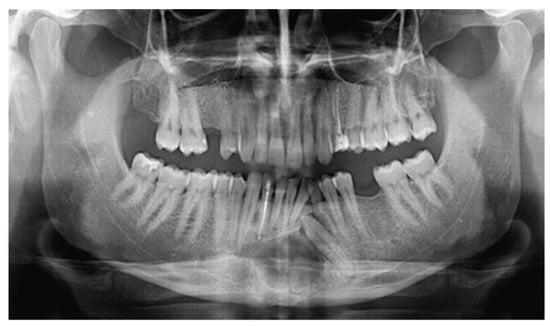

A 34-year old male presented to a private dental outpatient clinic with pus drainage and swelling in the III quadrant of the oral cavity, suggesting a dental infection. Collecting the medical history, the patient referred that 10 years before in an orthopantomography (OPG), an incidental finding of a radiotransparent lesion was documented (Figure 1). The mandible radiolucency was related to an impacted 33 dental element (left lower canine), a fact that had been compatible with the diagnosis of a dentigerous cyst (Figure 1). The patient was aware of the presence of this cystic lesion, but he had refused to remove it despite the dentist’s advice. For purulent discharge, the patient was treated with an antibiotic therapy (ceftriaxone 1g IM, 1 infiltration/day, for 1 week) prescribed by the private dentist. A cone-beam computed tomography (CBCT) of the mandible was also performed; no atypical radiologic signs were revealed (Figure 2). Nevertheless, a second episode of infection developed two months later, and it was treated again with antibiotic therapy prescribed by the private dentist (3 cycles of amoxicillin/clavulanate 1g per os) followed by ceftriaxone (1g IM, 1 infiltration/day, for 1 week) that we prescribed after our consultation for poor clinical response to previous treatment. The following month the patient had a new infective episode and was hospitalized in our department for further diagnostic investigations.

Figure 1.

During a routine orthopantomography (2007) performed 10 years before PIOSCC diagnosis, an impacted left lower canine, and a related incidental radiolucent cystic lesion was detected, compatible with the diagnosis of a dentigerous cyst.